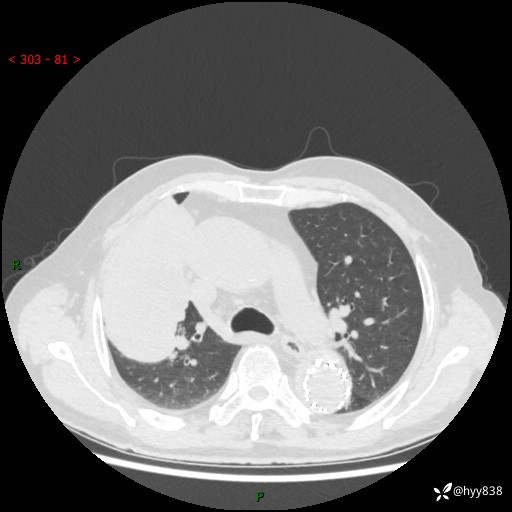

辅助检查:CT

胸部CT平扫